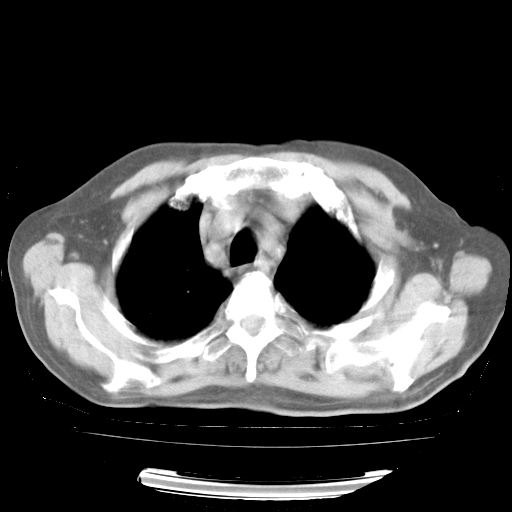

今天部分检查

轻微咳嗽,无痰,(体温正常时)R20次/分,P75次/分,双肺底、腋下可闻及少量捻发音。下肢轻度浮肿。

血常规:白细胞9.11×109/L,N0.92,L5.64,血小板39.2×109/L,HB148g/L,ESR2mm/H。

尿常规:潜血+

血生化:总蛋白69.71g/L,白蛋白38.40g/L,球蛋白31.31g/L,CRP27.9mg/L,尿素氮11.98mmol/L,肌酐106μmol/L,乳酸脱氢酶1099 U/L,肌酸激酶108U/L,CK-MB 61U/L。

腹部B超:胆囊壁增厚,肝、胆、胰、脾、肾无异常,肠系膜淋巴结、腹膜后淋巴结无增大。

ECG:右心室增大

心脏超声检查:无右心室增大。

增加治疗:异烟肼、利福平、乙胺丁醇,静滴左氧氟沙星、参麦注射液。甲强龙从80mg暂减为40mg。

强的松3月1日改为10mg qd,4月1日改为10mg qod。3月份以前的减量过程和环磷酰胺疗程需等明天查看记录(我岳父自己做的记录在他家里)。